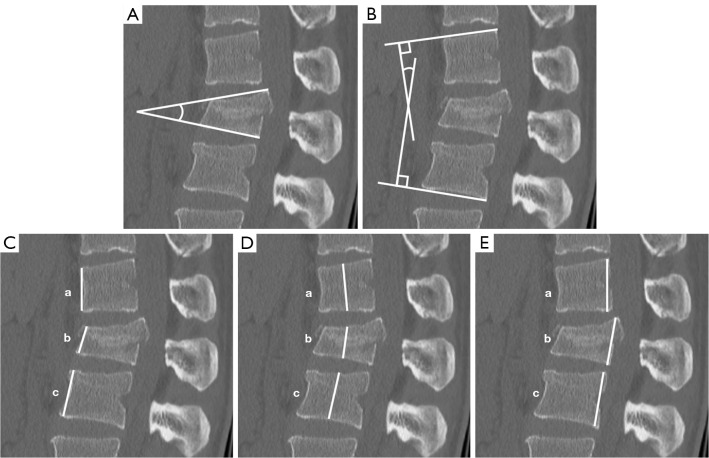

Methods: Twenty-five patients were included in the study. Age, gender, Injury severity score, level of fracture, AO classification, the McCormack Load sharing classification, and range of stabilization were collected. In addition, imaging assessment was performed to evaluate vertebral kyphosis angle, local kyphosis angle (Cobb angle), and the percentage of anterior, middle and posterior vertebral body compression at the time of injury and at the final follow-up after implant removal. The patients were divided into two groups, with and without RBP [Group RBP (+) and Group RBP (-), respectively]. Each variable was compared between groups. Cut-off values were calculated using the Youden index with receiver operating characteristic (ROC) curves.

Results: There were 12 patients in the RBP (+) group and 13 in the RBP (-) group. The two groups were significantly different only for the final local kyphosis angle, with no significant differences for the other variables. The ROC curve of the final local kyphosis angle for RBP had an area under the curve (AUC) of 0.88 (P<0.01). The optimal cut-off value for the final local kyphosis angle for RBP calculated from the Youden index was 15.85°.